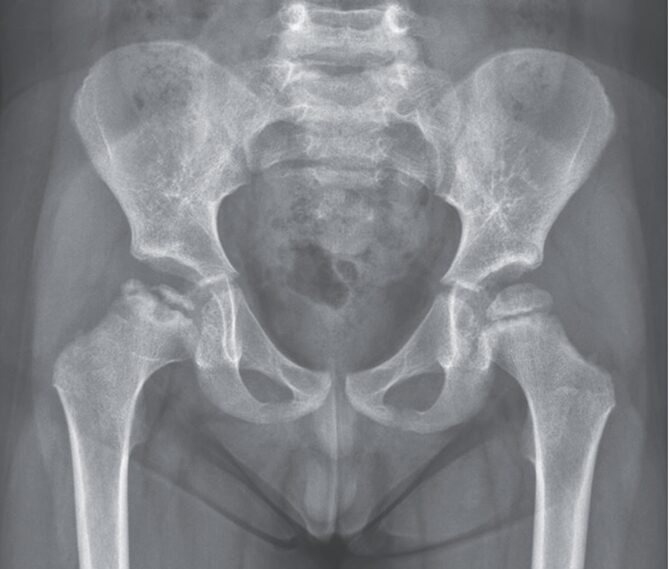

Xp施行。X-pでは右大腿骨頭の端部が圧壊されている所見が確認された。

「レッグ・カルベ・ペルテス病」と診断された。

レッグ・カルベ・ペルテス病は思春期前の小児における特発性大腿骨頭の無血管性壊死である。